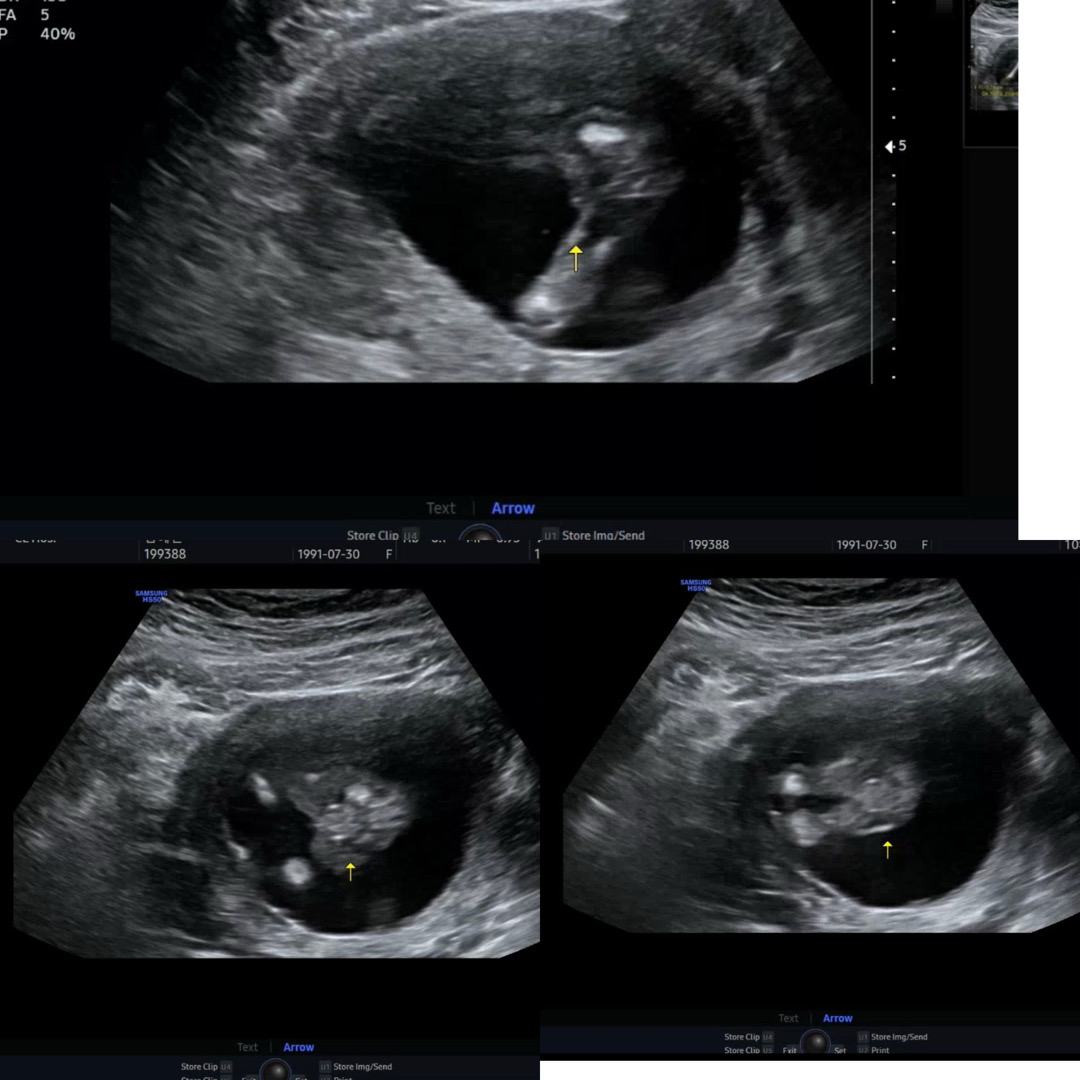

15주 3일차 성별 좀 봐주세요~ ㅠ

병원갔는데 정확히 말씀을 안해주셔서요 ㅠㅠ 딸인것 같은데 혹시 아들일수도 있을까요? 한번만 같이 봐쥬세요!!